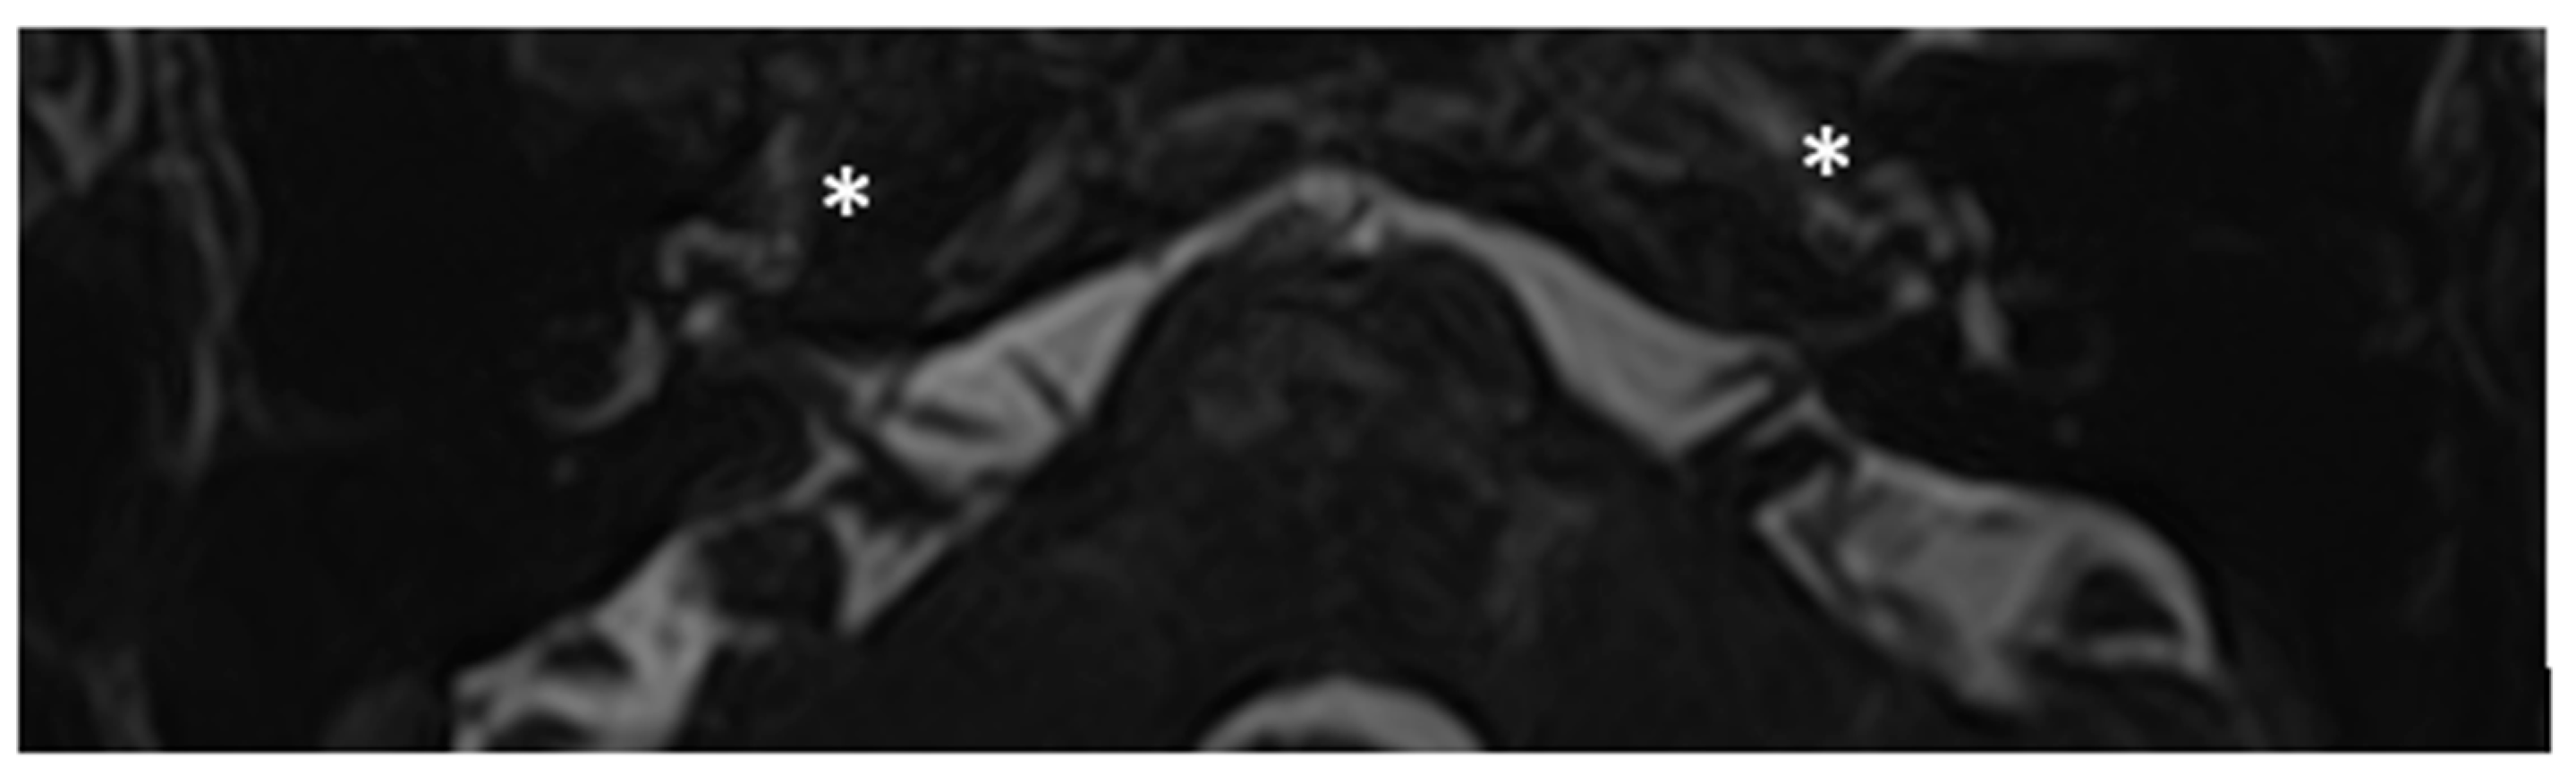

Within a few years, both ears showed progression of HL with worsening of bone threshold to SNHL bilaterally. In 2017 (27 years since diagnosis) she developed profound SNHL with left-sided anacusis and underwent cochlear implantation in the left ear. CT and MR images show a large cavity around the basal turn of the cochlea and massive osteorarefaction around the cochlea (‘double ring’ sign). The cavity appears to contain cerebrospinal fluid but does not communicate with the cochlear lumen (Figure 1 and Figure 2).

Figure 1. CT images of patient #1 with osteogenesis Imperfecta. A and B, right side in axial plane. C and D, right side in coronal plane. E and F, left side in axial plane. G and H, left side in coronal plane. A pericochlear cavity is visible in all figures;. arrows indicate its origin from the IAC. Asterisks indicate extension of osteorarefation into the cochlea.